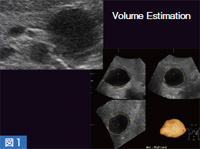

通常,2Dで腫瘍や嚢胞の体積計算を行う場合は,縦,横,厚みの3方向を計測して割り出しているが,計測位置がずれると数値が大きく変化してしまうことがある。一方,3Dでは,プローブのスイープ角の中に嚢胞がすべて納まるように設定すると,5秒以内で3Dの断面像として表示される。嚢胞のみをボリュームレンダリング(VR)表示することも可能であり(図1),エコーレベルのコントラストが十分に得られる症例では,例えばがんの化学療法や放射線治療後の経過観察などにおいて,体積の変化が視覚的に判断できるようになる。また,VR表示された嚢胞は,回転させてさまざまな方向から観察可能であり,嚢胞を取り出して内腔面の凹凸を見ることもできる。

図1